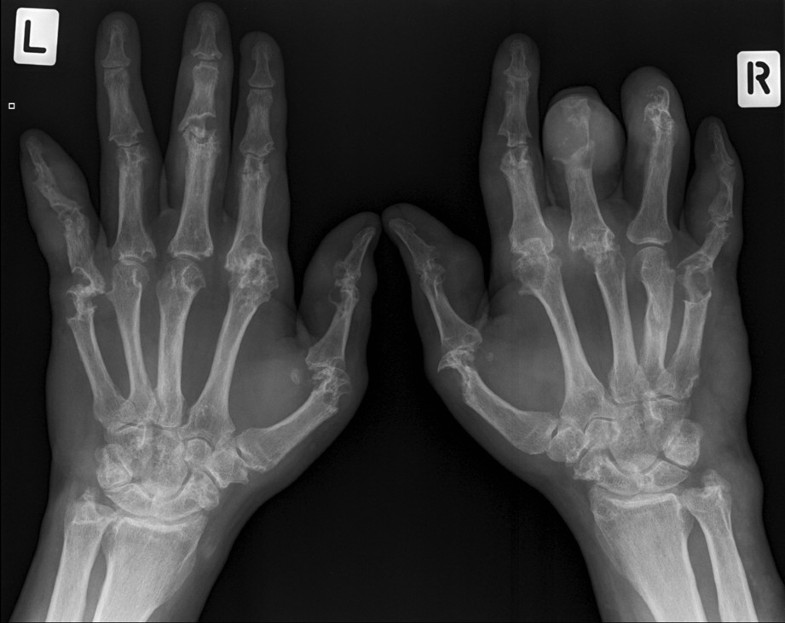

Gout Ankle Xray Foot Gout Mri mri is helpful in the localization of gout deposit and can show gout in the deeper tissues like the spine. mri of gout magnetic resonance (mr) findings in gout include erosions, reactive bone marrow. while mri is not a new imaging technique, recent investigations into mri in gout have altered our understanding of the disease. gout. Foot Gout Mri.

Gout Arthritis Foot Radiology at Joseph Rice blog Foot Gout Mri mri of gout magnetic resonance (mr) findings in gout include erosions, reactive bone marrow. while mri is not a new imaging technique, recent investigations into mri in gout have altered our understanding of the disease. gout is an inflammatory arthritis and any joint can be involved in gout, but the first mtp joint is the most common.. Foot Gout Mri.

Gout Arthritis Foot Radiology at Joseph Rice blog Foot Gout Mri while mri is not a new imaging technique, recent investigations into mri in gout have altered our understanding of the disease. mri is helpful in the localization of gout deposit and can show gout in the deeper tissues like the spine. mri of gout magnetic resonance (mr) findings in gout include erosions, reactive bone marrow. gout. Foot Gout Mri.